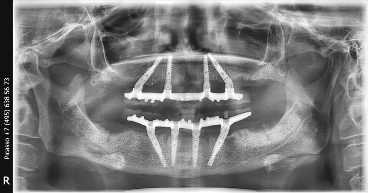

All-on-4 на рентгеновских снимках

![]() |